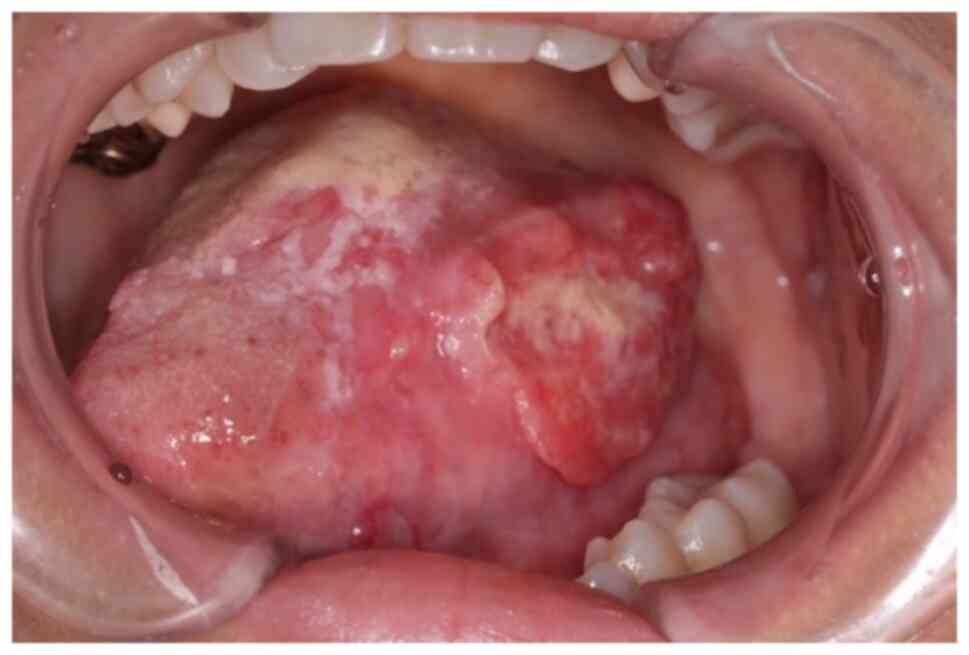

The ECAS system can superselectively administer anticancer drugs to numerous feeding arteries from the superficial temporal artery: A case report and literature review

Superselective intra‑arterial chemoradiotherapy (SSIACRT) is one of the curative treatments for advanced oral cancer. SSIACRT can reportedly treat cervical lymph node metastases in the level I‑IIA area by super selectively catheterizing the facial artery (FA) and infusing drugs. However, since advanced oral cancer lesions involve a number of feeding vessels, retrograde treatment requires the placement of catheters from the superficial temporal artery (STA) and occipital artery (OA). Furthermore, in the case of level IIB lymph node metastasis, the catheter must be changed because it is necessary to administer anticancer drugs to more than three routes, including the OA, when the feeding arteries of the primary tumor are combined. The external carotid artery sheath (ECAS) system used in the present study involves the insertion of a microcatheter or steering catheter from one route of the STA, allowing selection of numerous feeding vessels, including the OA. The ECAS system can facilitate the administration of chemotherapy via the STA simultaneously to the maxillary artery, lingual artery, FA and OA. The present study describes cases of maxillary gingival cancer and tongue cancer with cervical lymph node metastasis, which were treated with the ECAS system via the STA; the treatment successfully controlled both the primary tumor and cervical lymph node metastasis. In the two cases described in the present study, metastatic lymph nodes were found in the level ⅠB and ⅡB region, but were successfully treated by administering cisplatin via the OA, in addition to the primary lesion. To date, to the best of our knowledge, there is no case report clearly referring to the treatment of lymph node metastasis using the ECAS system. In conclusion, SSIACRT using ECAS may be considered a useful treatment for oral cancer with cervical lymph node metastasis.